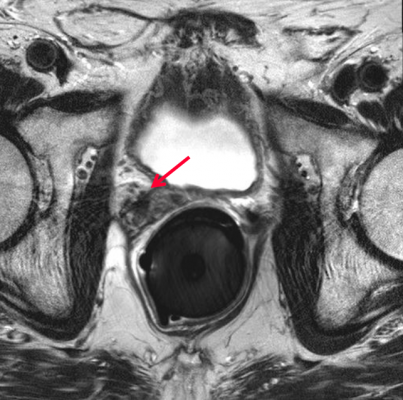

Prostate cancer is the second most common cancer in U.S. men. An estimated 161,300 new cases will be diagnosed and nearly 27,000 deaths are expected in 2017, according to the American Cancer Society.

More than 30 percent of prostate cancer patients face the return of disease one to four years after removal of the prostate gland, Sandler said.

When a patient experiences a recurrence, physicians typically prescribe radiation therapy. “Our results show that adding hormone therapy could add years to patients’ lives,” Sandler said.